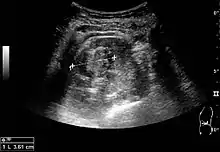

Figure 5. Simple renal cyst with posterior enhancement in an adult kidney. Measurement of kidney length on the US image is illustrated by '+' and a dashed line.[1]